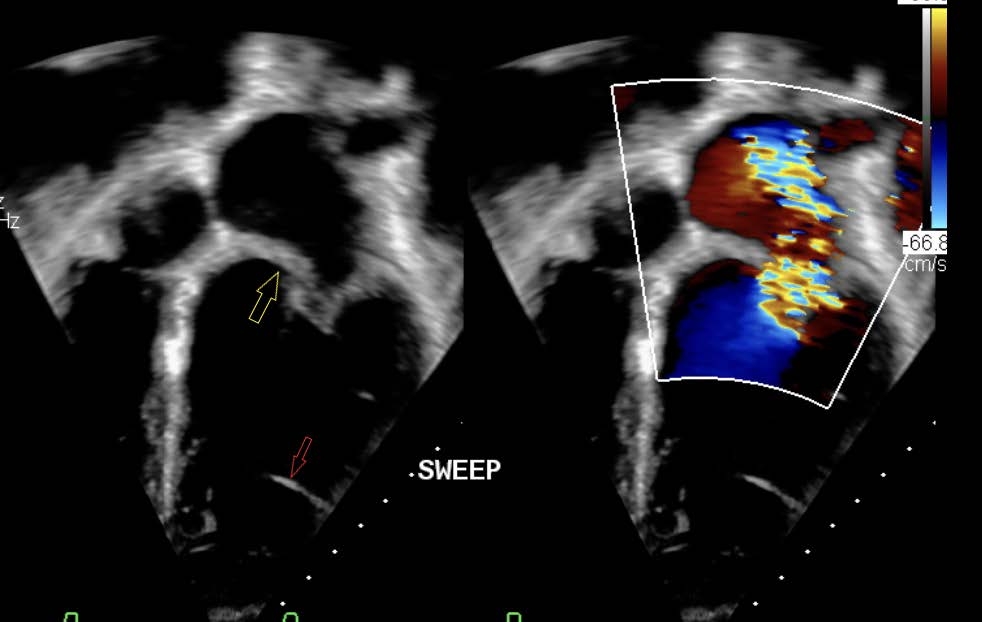

Echocardiogram showed a dysplastic mitral valve with severe regurgitation and moderate left ventricle dilation with normal systolic function (figure 2). MRI confirmed these findings. The patient underwent subsequent surgical replacement of the mitral valve with excision of the observable remnant of the LVFT. Post-operatively, runs of ventricular tachycardia ceased, and ventricular ectopy burden became infrequent (<0.1%). Amiodarone was weaned without increase in ventricular ectopy or VT recurrence.